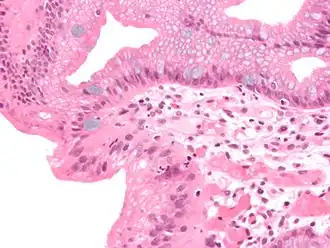

![]() Гистологическая картина пищевода Барретта | |